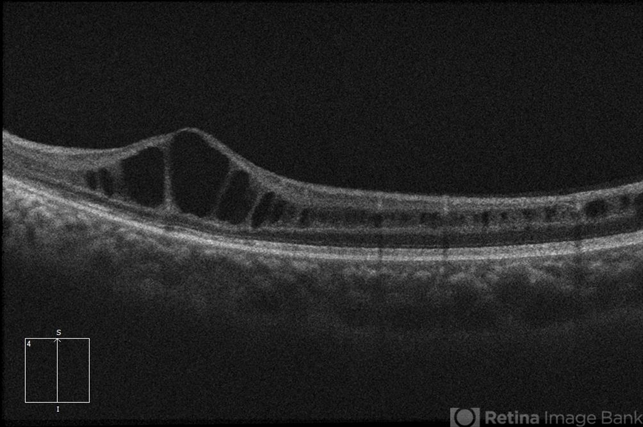

- retinoschisis

Optical coherence tomography system

Zeiss Cirrus 5000 - Description

- 21-year-old male with congenital retinoschisis with bilateral macular involvement and large inner retinal hole OD.